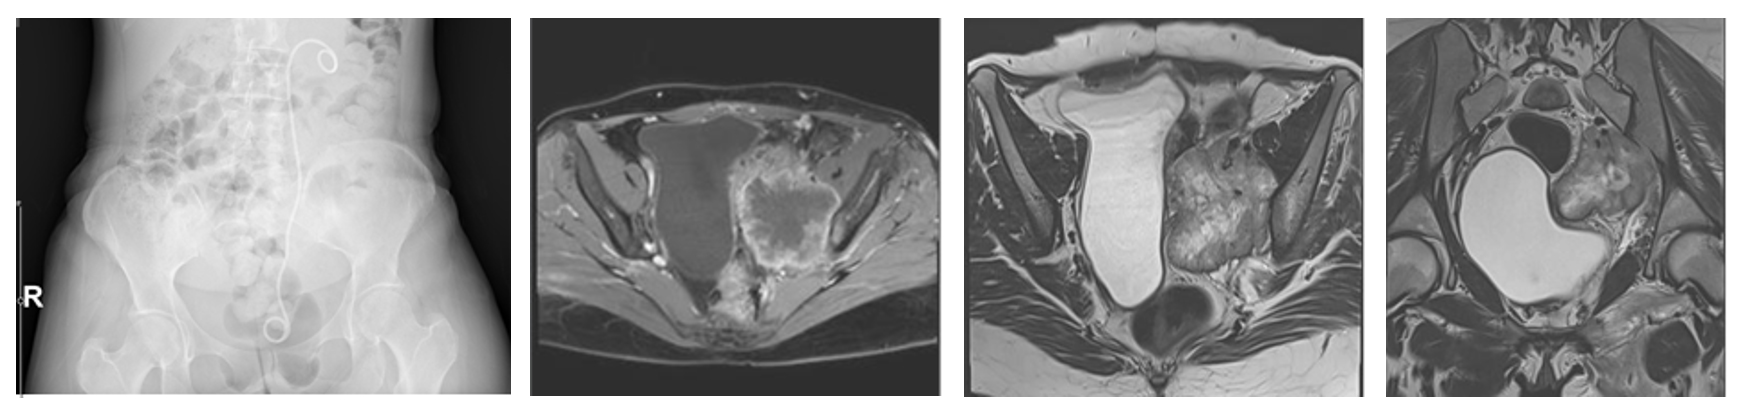

Ameliyat Öncesi: Röntgende sol üreterde katater dışında anlamlı görüntü yok iken MR’da sol sakroiliak eklem seviyesinde düzensiz sınırlı içinde gaz gölgesi olan ve mesaneyi iten büyük yumuşak doku kitlesi görülmekte.